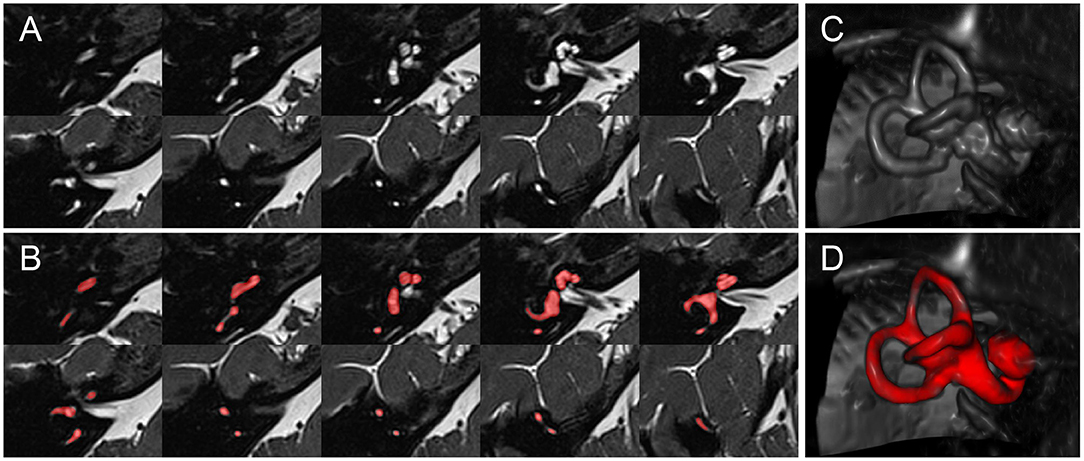

• Segmentation : On cherche ici à isoler un élément dans une image 2D ou 3D. Prenons l’exemple d’une IRM du cerveau dans laquelle on souhaite localiser l’oreille interne. L’objectif est d’obtenir un masque de valeurs 0/1 indiquant les voxels appartenant à l’oreille interne. Pour cela, le réseau produit en sortie un tenseur 3D de mêmes dimensions que l’IRM d’origine. Ces valeurs, sous forme de nombres réels, sont ensuite seuillées (par exemple à 0.5) afin de construire le masque final.

../_images/ie.jpg